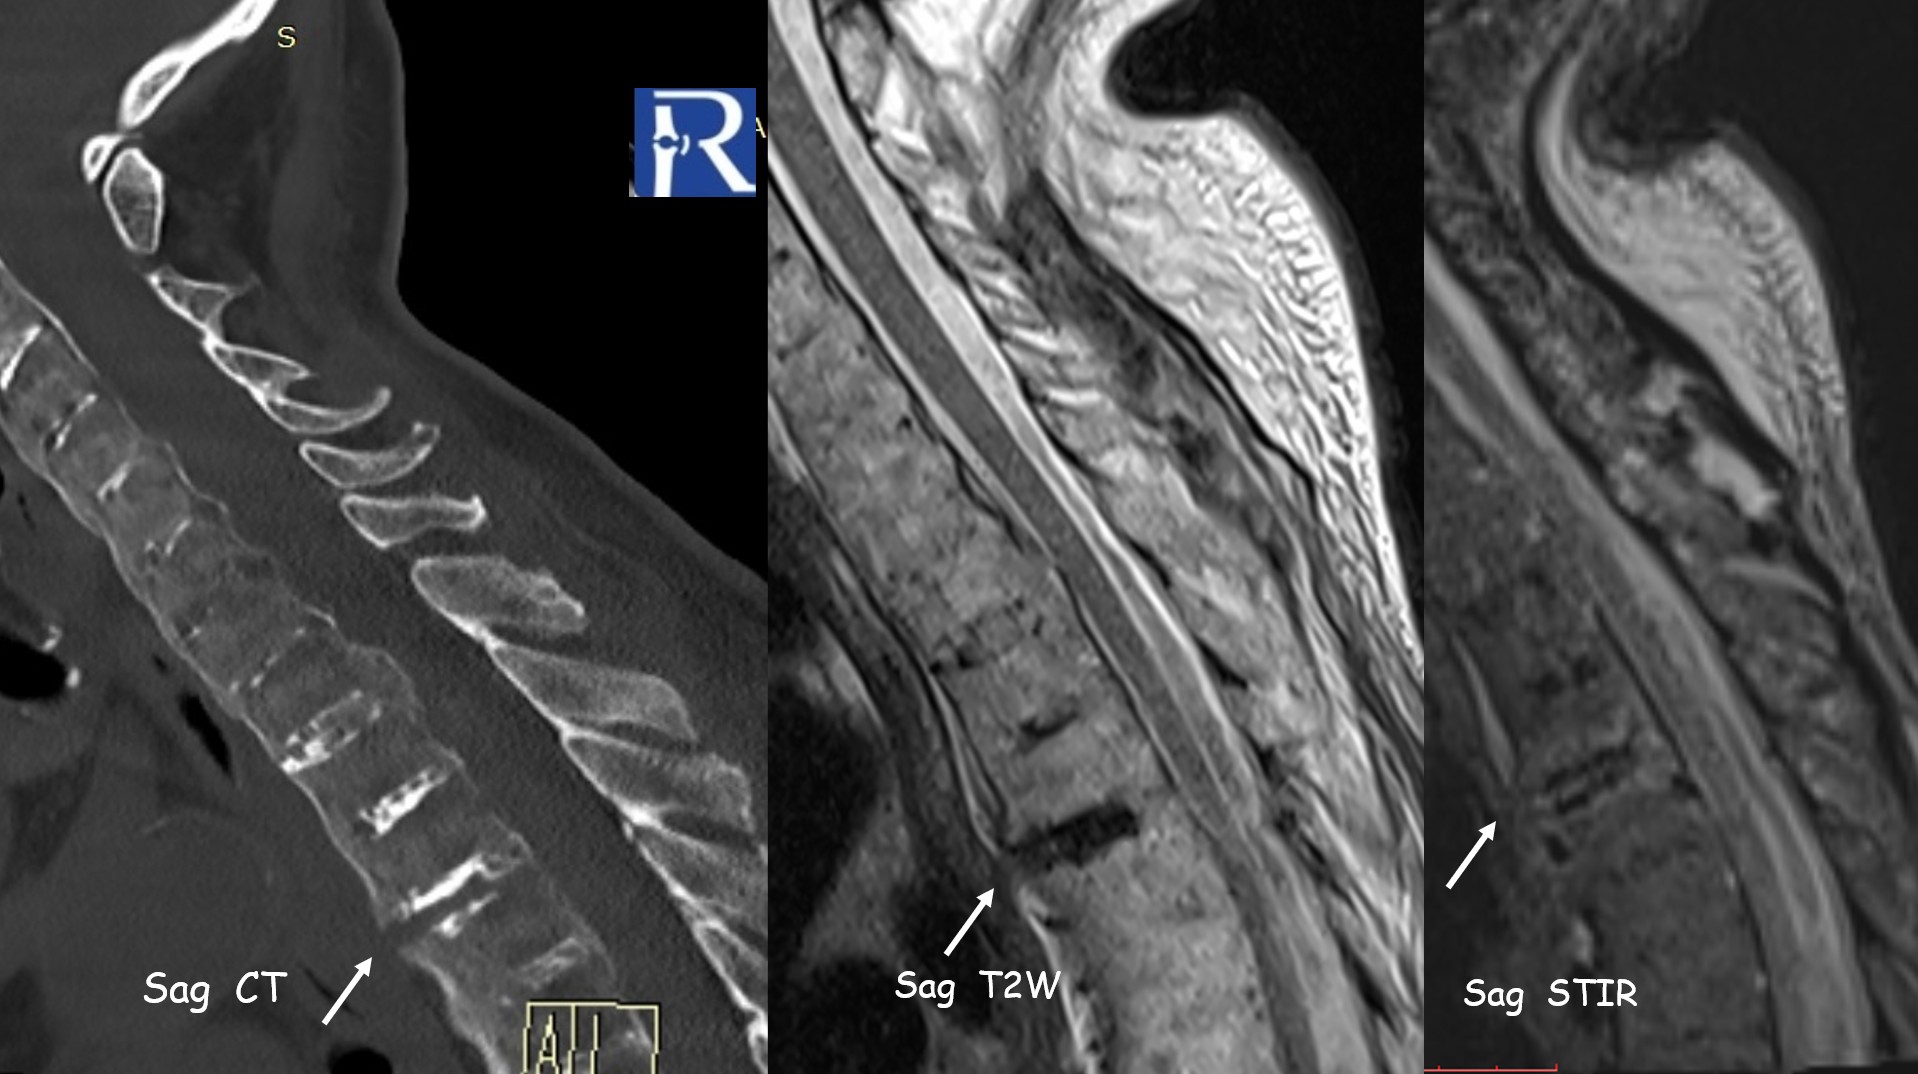

Clinical Background A 77-year-old patient with Ankylosing Spondylitis presented after a low-energy fall with acute thoracic pain. Imaging Findin ...

Case Summary A 70-year-old male presented with shoulder pain after a fall. Initial computed tomography (CT) demonstrated a linear, nondisplaced fra ...